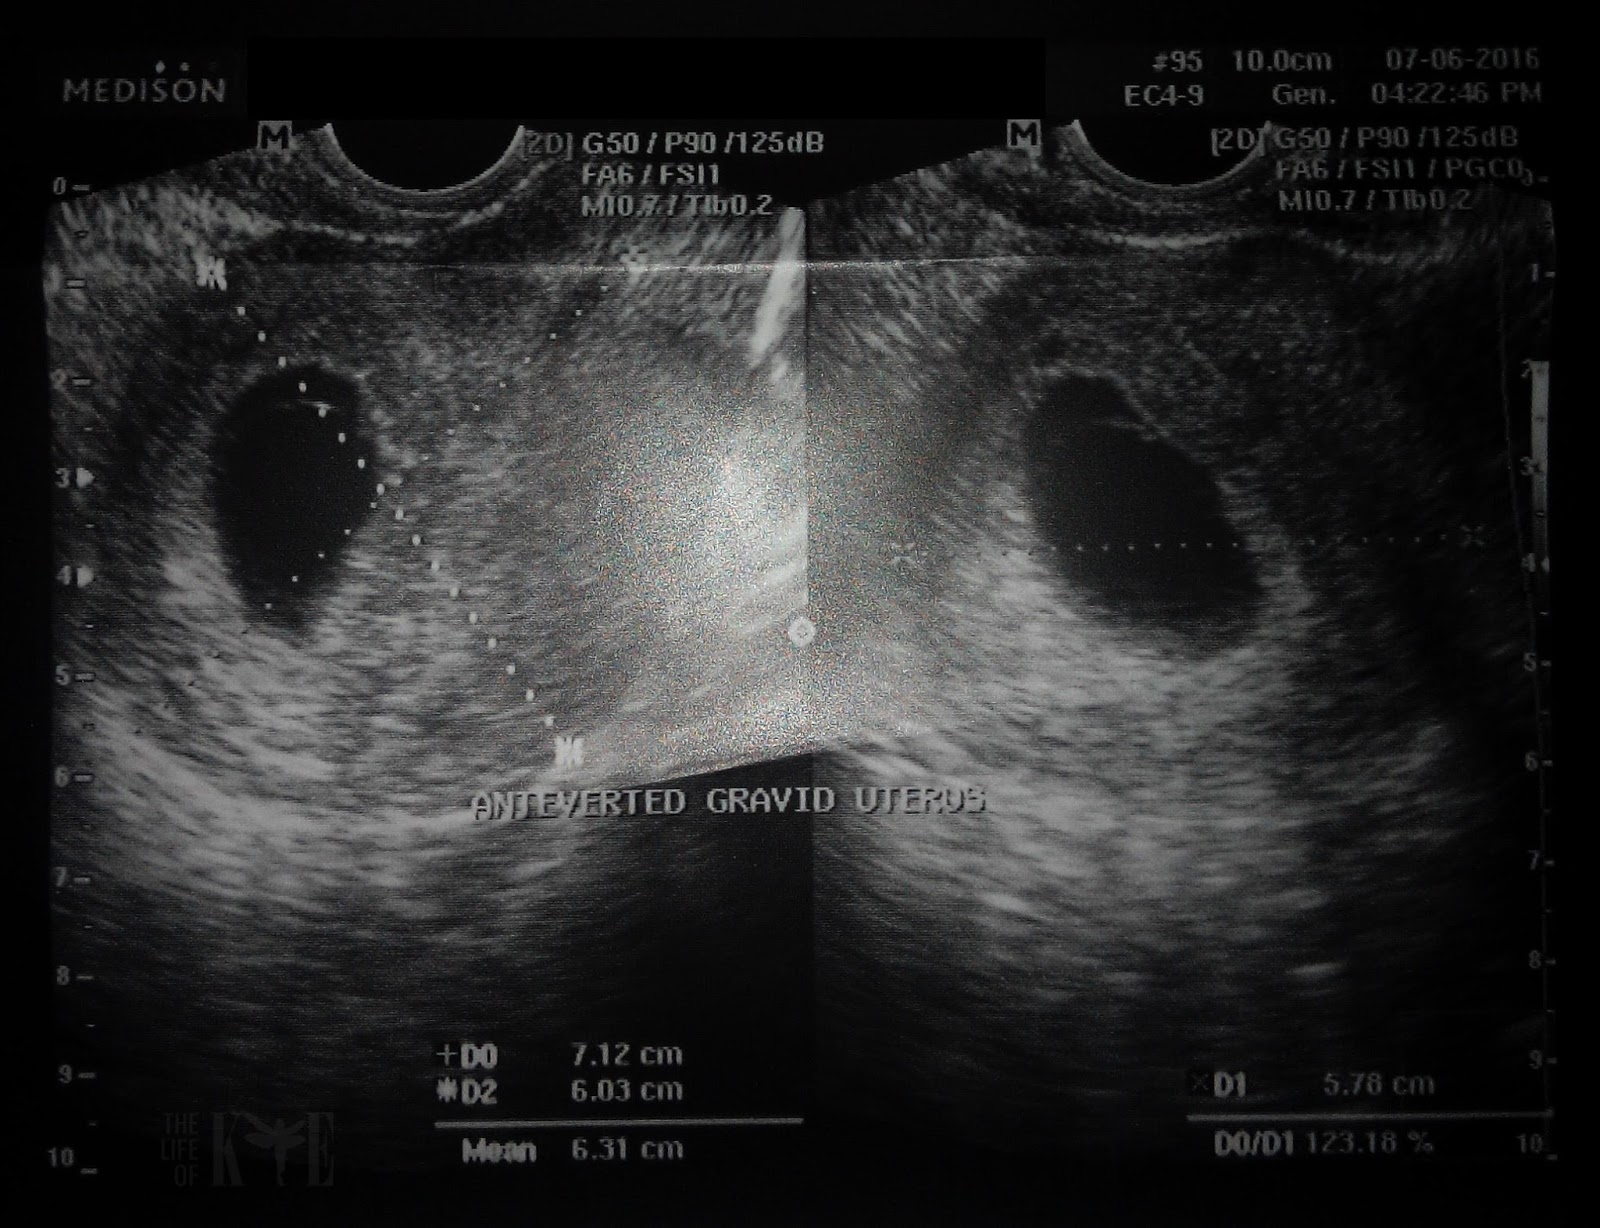

9 weeks + 2 days - first ultrasound

I fought the urge to post the scans in social media because there's nothing much to see yet. We were advised to repeat the scan after a week.

My gestational age was estimated at 7 weeks 2 days, 2 weeks after my LMP according to the size of the gestational sac.

Maybe I conceived later than I thought. No big deal.

Gravid = means pregnant

Anteverted = tilted forward, more common among women

Yolk sac was only 0.35 cm.

The baby may either be too small to be detected, is slowly growing, or it could mean that the growth stopped and it could be a blighted ovum.

It was hard to sleep that night but I kept telling myself it's not final yet.